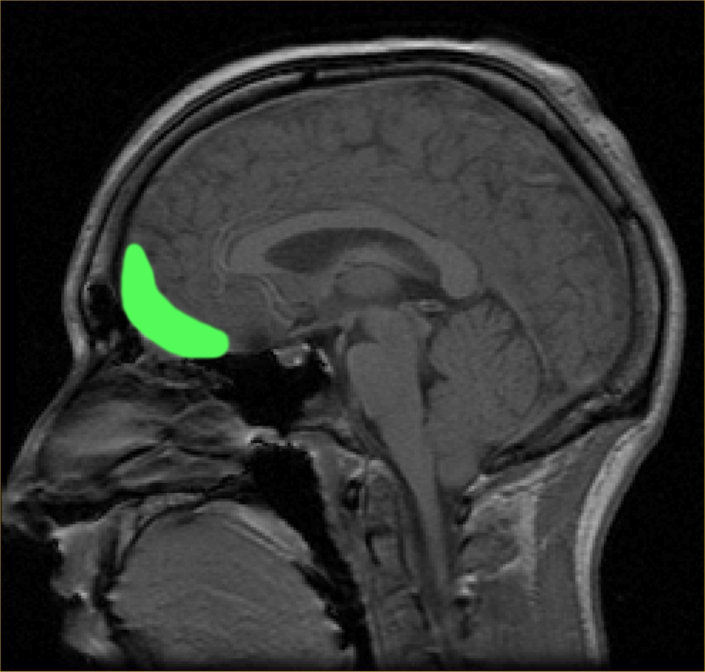

2. LAS ÁREAS DE BRODMAN

1. Síndrome prefrontal dorsolateral

2. Síndrome prefrontal Orbital

2. Síndrome medio basal y cingular